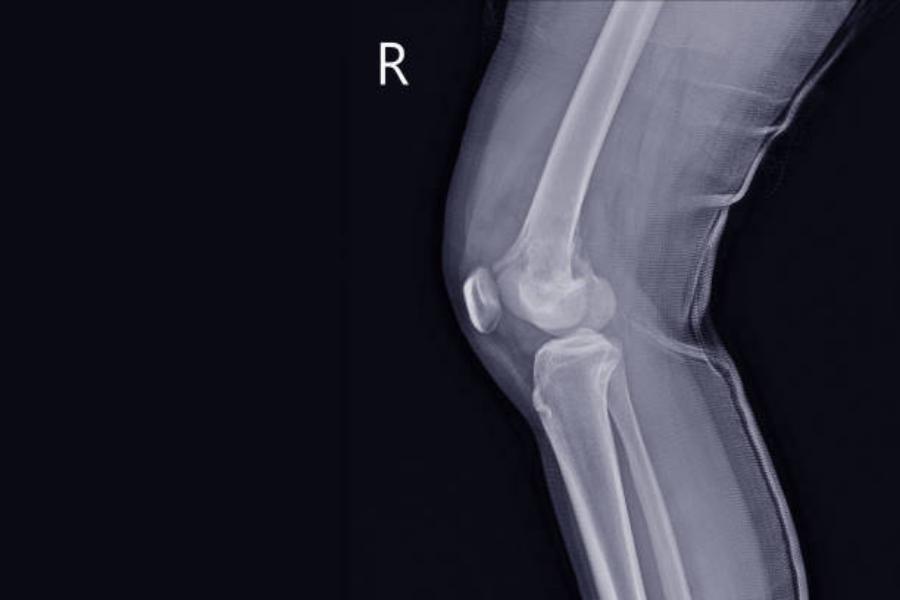

El sarcoma de tejido óseo tiene su origen en el tejido conjuntivo, que es el conjunto de células que forman la estructura del cuerpo humano. Existen diferentes tipos de sarcomas óseos: osteosarcoma, condrosarcoma, sarcoma de Ewing y otros sarcomas. Este tipo de tumor afecta en especial a niños y adolescentes, así como a las personas mayores de 65 años. El sarcoma de tejidos blandos afecta a los tejidos adiposos, musculosos, nerviosos y fibrosos, así como a los vasos sanguíneos. La mayoría se originan en brazos y piernas, aunque también pueden aparecer en la cabeza, tronco u órganos internos, entre otros.